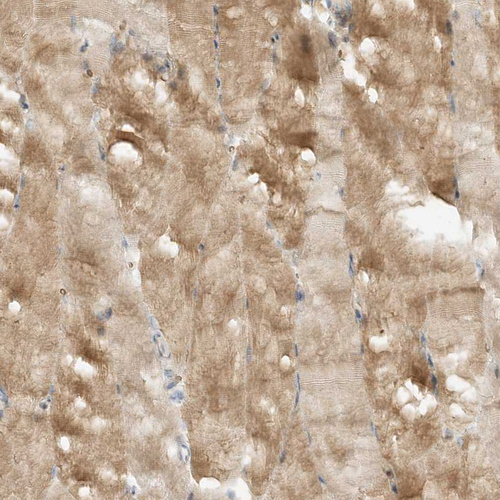

Immunohistochemical staining of human heart muscle shows weak cytoplasmic positivity in cardiomyocytes.